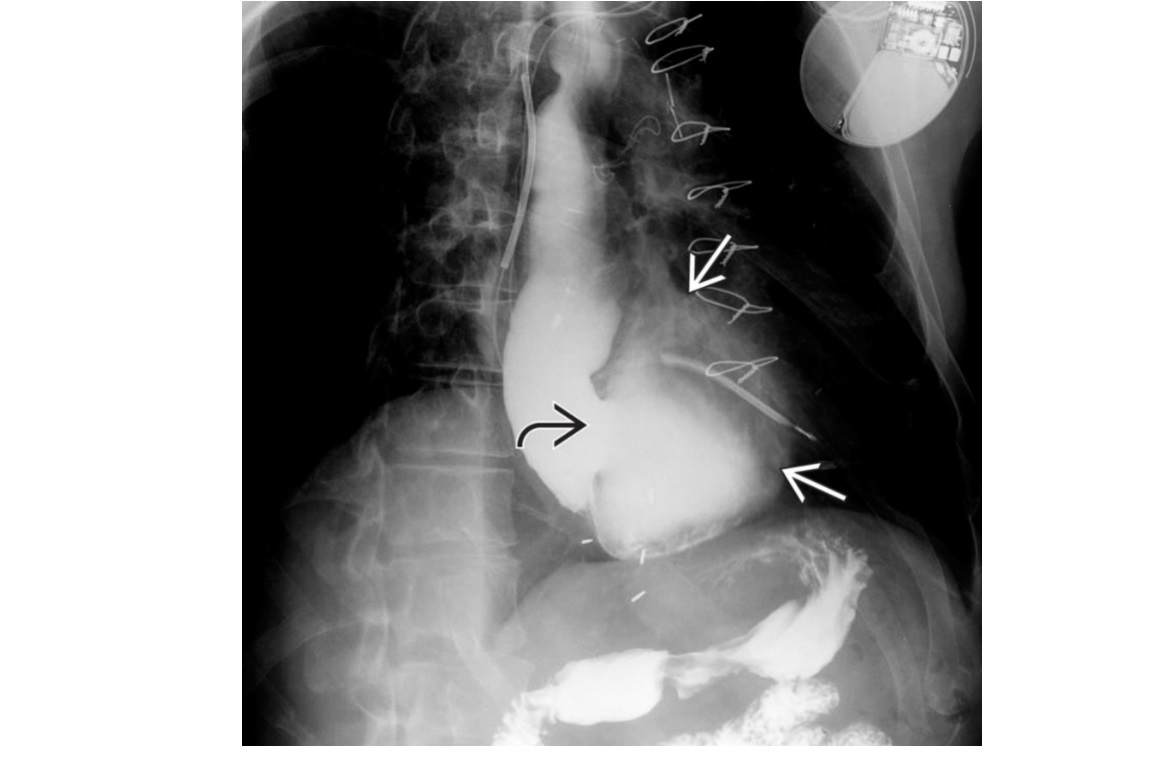

Caustic

long stricture ± diffuse ulceration of lower and mid oesophagus

Stomach can be pulled into the chest as the oesophagus shortens and strictures

DDX Long stricture

-NG tube in too long or radiation - These are usually smooth

1. Organoaxial

- Greater curvature flips over the lesser.

- Older people

- Associated with paraesophageal hernia

2. Mesenteroaxial

- Twisting over the mesentery

- ischaemia, obstruction

- kids